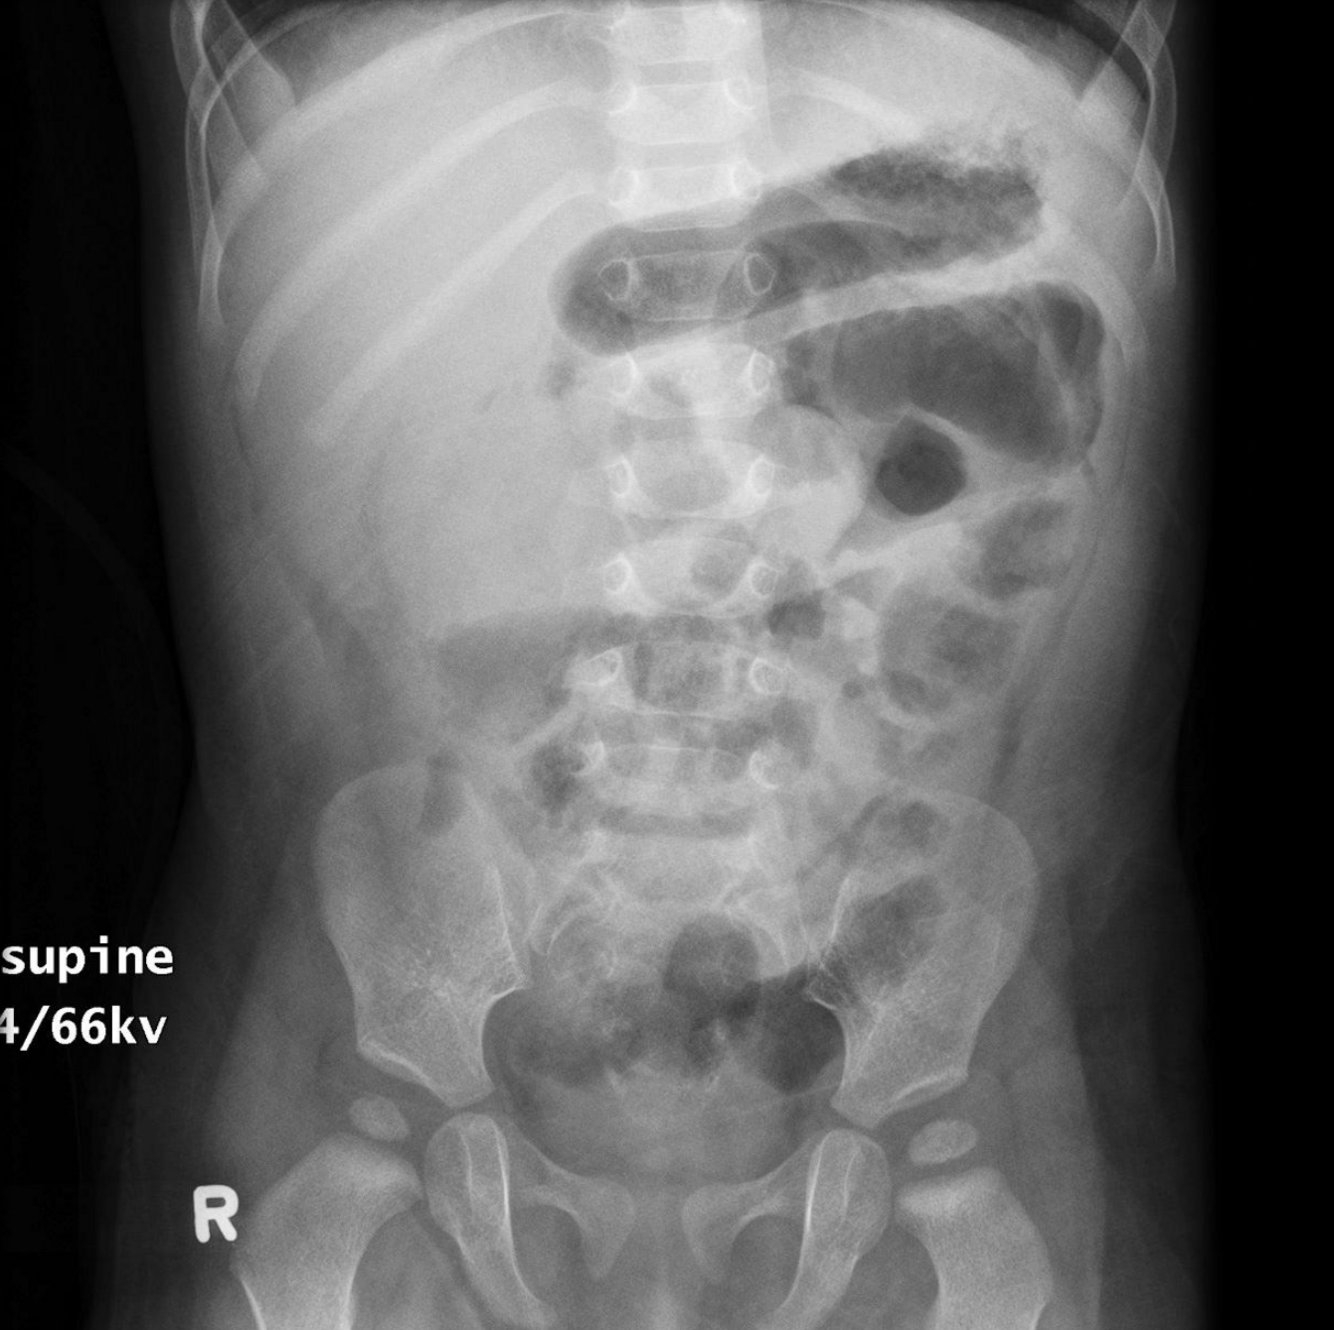

two positives and two negatives?

A

Positives

* dilated small bowel loops

* thumbprinting

Negatives

* no fecal loading

* no free air

* no rigleers sign